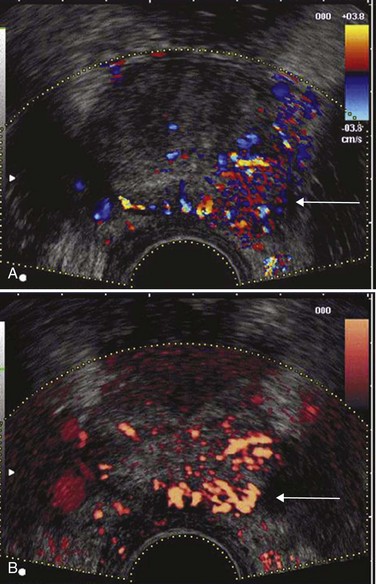

Color Doppler imaging is based on the frequency shift in the reflected sound waves from the frequency of insonation and thus depicts the velocity of blood flow in a directionally dependent manner (Fig. 97–6A). Color assignment is based on the direction of blood flow related to the orientation of the transducer receiving the signal; flow toward the transducer is depicted in shades of red and flow away in shades of blue; the color is not specific for arterial or venous flow. Power Doppler imaging (also known as enhanced color Doppler, color amplitude imaging [CAI], or color angiography) uses amplitude shift to detect flow in a velocity and directionally independent manner (Bude and Rubin, 1996) (see Fig. 97–6B). The advantages of power Doppler imaging are its ability to detect slower flow and to have less reliance on the Doppler angle, making it more suitable for detection of prostate cancer neovascularity. Although power Doppler imaging offers improved sensitivity to small amounts of flow, neither modality has yet proved itself superior to the other for cancer detection. In 251 patients, Halpern and Strup (2000) found color Doppler sensitivity and specificity of 14.6% and 93.9%, respectively, to identify cancer. Whereas Doppler modes showed an improved diagnosis versus gray-scale TRUS, 45% of cancers still went unidentified by any sonographic modality. Others have shown increased cancer detection rates using Doppler-targeted biopsy strategies (Kelly et al, 1993; Rifkin et al, 1993; Newman et al, 1995; Sakarya et al, 1998; Cornud et al, 2000; Okihara et al, 2000; Shigeno et al, 2000), but none is sufficiently accurate to replace systematic biopsy (Halpern et al, 2002a). Enhancements in the technical aspects of color Doppler TRUS, including the use of contrast agents (see later), may provide the necessary improvements to specifically identify cancer sites in the future.

Figure 97–6 Color Doppler (A) transrectal ultrasonography (TRUS) and power Doppler (B) TRUS identify a Gleason 4 + 4 = 8 adenocarcinoma in the left midgland.

Multiple studies have shown that angioneogenesis and the resultant increase in microvessel density that occurs within foci of prostatic adenocarcinoma correlates with the presence of metastasis (Weidner et al, 1993), stage of disease (Fregene et al, 1993; Brawer et al, 1994; Bostwick et al, 1996), and disease-specific survival (Lissbrant et al, 1997; Borre et al, 1998). Interest in using color and power Doppler TRUS to aid in prostate cancer detection stems from studies of radical prostatectomy specimens demonstrating that foci of adenocarcinoma possess an increased density of microvessels compared with surrounding normal parenchyma (Bigler et al, 1993).

Patients with detectable color Doppler flow within their dominant tumor at the time of TRUS-guided biopsy are at a 10-fold increased risk for PSA recurrence after radical retropubic prostatectomy (Ismail et al, 1997). The presence of increased flow was also associated with a higher Gleason grade, increased incidence of SV invasion, and a lower biochemical disease-free (bNED) survival rate versus subjects without increased flow on preoperative TRUS (50% vs. 96% bNED at 31 months) (Ismail et al, 1997). Other investigators have also shown the association of power Doppler flow signals as an indicator of microvessel density with a higher Gleason score and have suggested a correlation with outcome (Wilson et al, 2004).